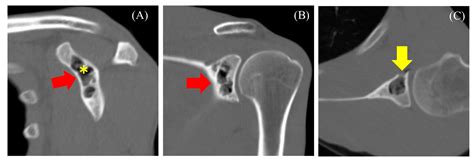

• slap tear with paralabral cyst

• paralabral cyst

• cyst in shoulder rotator cuff